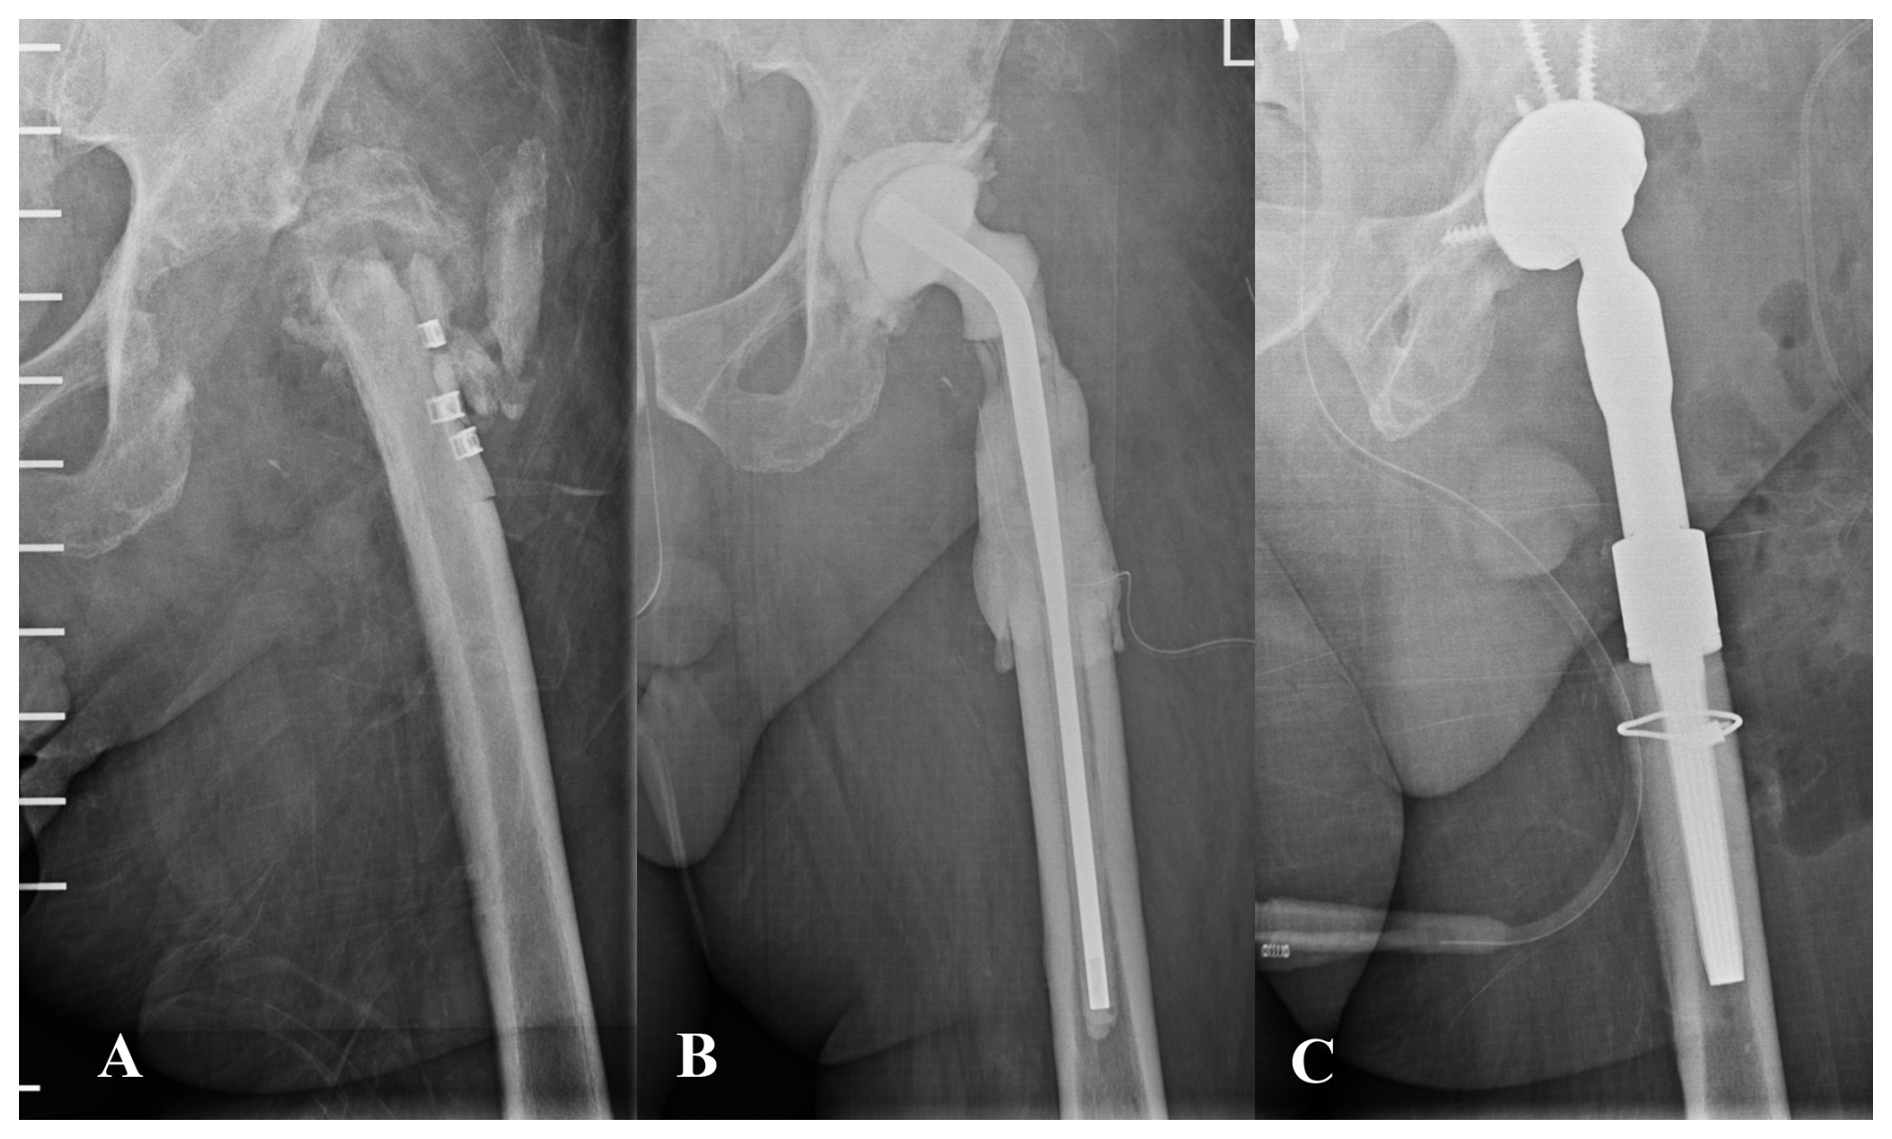

https://jbji.copernicus.org/articles/11/43/2026/jbji-11-43-2026-f03

Figure 3(A) Anteroposterior pelvic radiograph of a patient with chronic prosthetic joint infection of the left hip. The patient had previously undergone multiple procedures involving osteosynthesis material. Both the patient's medical history and the diffuse radiographic appearance of the proximal femur suggested bone involvement compatible with osteomyelitis. (B) A wide resection of the proximal femur was undertaken, and a preformed spacer was implanted. Histological analysis revealed mild neutrophil infiltration and chronic inflammatory changes within trabecular bone and bone marrow, consistent with osteomyelitis. (C) Hip reconstruction was subsequently performed using a megaprosthesis owing to the substantial bone loss in the proximal femur. This procedure may also be undertaken in a one-stage approach, although accurately determining the true extent of femoral bone involvement can be challenging.